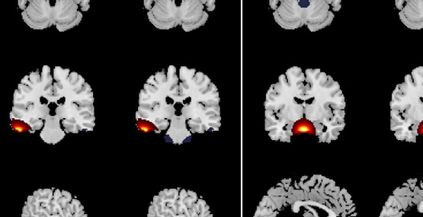

In the last two decades, unsupervised latent variable models---blind source separation (BSS) especially---have enjoyed a strong reputation for the interpretable features they produce. Seldom do these models combine the rich diversity of information available in multiple datasets. Multidatasets, on the other hand, yield joint solutions otherwise unavailable in isolation, with a potential for pivotal insights into complex systems. To take advantage of the complex multidimensional subspace structures that capture underlying modes of shared and unique variability across and within datasets, we present a direct, principled approach to multidataset combination. We design a new method called multidataset independent subspace analysis (MISA) that leverages joint information from multiple heterogeneous datasets in a flexible and synergistic fashion. Methodological innovations exploiting the Kotz distribution for subspace modeling in conjunction with a novel combinatorial optimization for evasion of local minima enable MISA to produce a robust generalization of independent component analysis (ICA), independent vector analysis (IVA), and independent subspace analysis (ISA) in a single unified model. We highlight the utility of MISA for multimodal information fusion, including sample-poor regimes and low signal-to-noise ratio scenarios, promoting novel applications in both unimodal and multimodal brain imaging data.